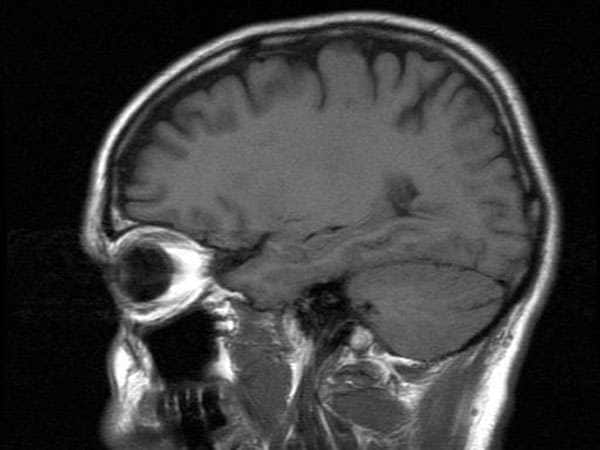

Topics featured on the Life’s Little Mysteries website include body and mind, earth, space and weather, animals and the “just plain strange.”

Topics featured on the Life’s Little Mysteries website include body and mind, earth, space and weather, animals and the “just plain strange.”